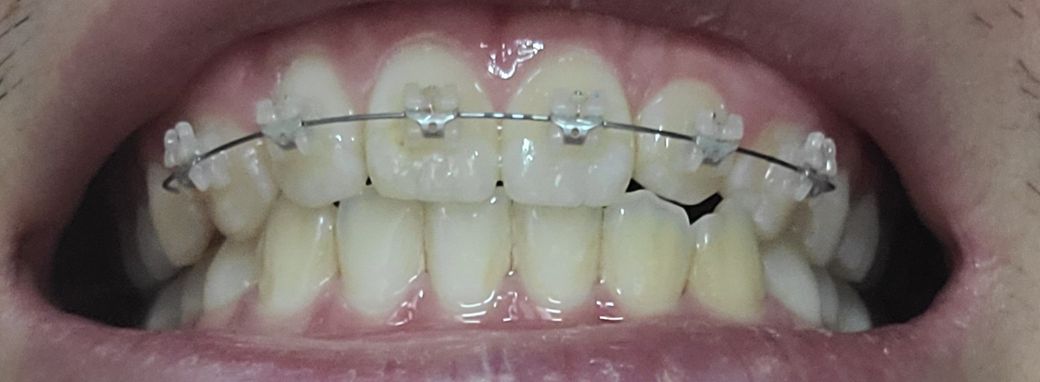

저는 앞뒤로 공간이 없어보이는데 치아가 마모될수도 있을까요 제앞니 어떼보이시나요?

이를 앙 다물고 찍은 사진입니다

절단 교합은 상 하악 앞니가 정확히 일직선으로 맞물려야 합니다. 따라서 지금 정도로 절단교합이라고 하지 않습니다. 또한 음식 섭취 시 앞니는 음식을 간단히 끊는 용도이지 실제로는 어금니가 모든 역할을 합니다. 따라서 해당 치아가 현재로 맞물린다고 해서 마모되지 않습니다. 지금 정도는 교정 중이기 때문에 잘못되었다고 볼수도 없고 절단교합 및 이상이라고 하지 않습니다. 치료를 충실히 받으시길 바랍니다.

사진으로는 오른쪽은 절단교합이 아닌 정상교합이며, 왼쪽은 측절치가 애매하게 보이긴 합니다.

말그대로 절단교합은 앞니 끝과 아래니의 끝이 교합이 되는 상태를 말합니다. 사진상으로 보면 절단교합은 아니신거 같아요.